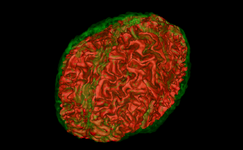

Robust Statistical Segmentation (Yi Gao)